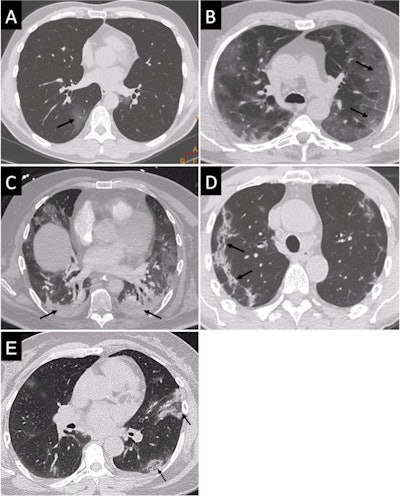

Readers rated chest CTs as "Surely COVID+," when patients presented with peripheral, bilateral, or multifocal ground-glass opacity (GGO) of rounded morphology and/or consolidation or crazy paving, reversed halo sign, or subpleural bands of consolidations. They classed scans as "Possible COVID+," when they had multifocal, diffuse, peripheral, or unilateral GGO and/or consolidation lacking a specific distribution or showed only few very small GGO with a nonrounded and nonperipheral distribution or when there were atypical findings, such as large pleural effusion, major lymph node size increase, or bronchiolitis pattern. Scans were deemed "COVID−" when the chest CT was normal or demonstrated another pathology.

Among the 694 patients, 287 were positive on the final RT-PCR exam. From the 694 chest CTs, 308 were rated as "Surely COVID+", 34 as "Possible COVID+," and 352 as "COVID−." When considering only the "Surely COVID+" CT as positive (the other two classes being deemed negative), accuracy, sensitivity, specificity, PPV, and NPV reached 88.9%, 90.2%, 88%, 84.1%, and 92.7%, respectively, with respect to the final RT-PCR test. Agreement between the two methods was good, with a kappa of 0.77 (95% confidence interval [CI] 0.73-0.82).